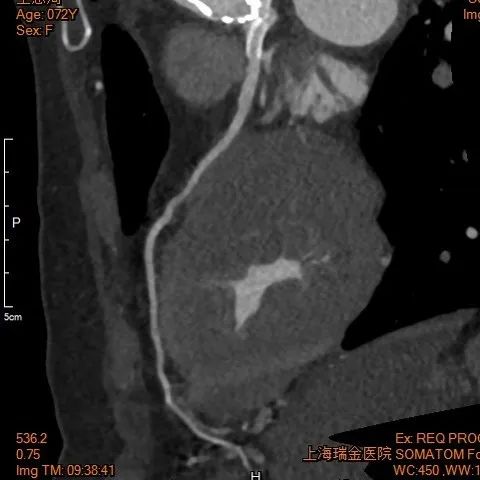

术后1w——冠脉CTA

术后24h心超

● EF 68% 。

● 主动脉瓣未见明显反流。经主动脉瓣口收缩期最大流速约1.9m/s,最大压差约15mmHg,心率约95bpm。